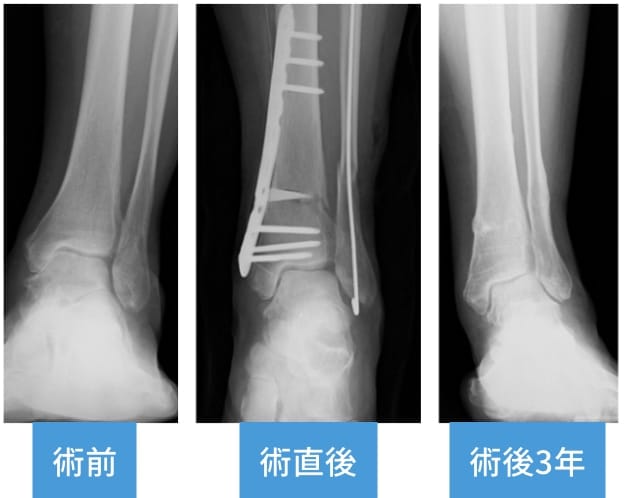

足関節の内くるぶし側のみの軟骨損傷の場合に適応になることが多いです。骨を切って楔状の人工骨を入れ、足関節の角度を変えてプレートで固定します。足関節の角度が変わることで内くるぶし側への荷重が減り、痛みが緩和します。手術後は5週間ほどギプスで固定して、骨がしっかりとついたらプレートを抜去します(術後約1年)。